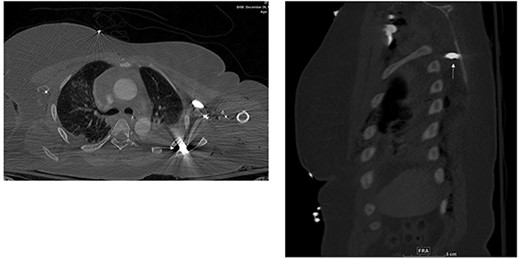

Chest CT showed three bullet fragments. One was adjacent to the right acromioclavicular junction, another was posterolateral to the right periscapular muscles, and the third was anterior to the left scapula (Fig. 4). In addition to right lung contusions, left fifth rib fracture with pneumothorax, and bilateral pleural hemothorax more at the left side.

Bullet fragments adjacent to the right acromioclavicular junction and posterolateral.